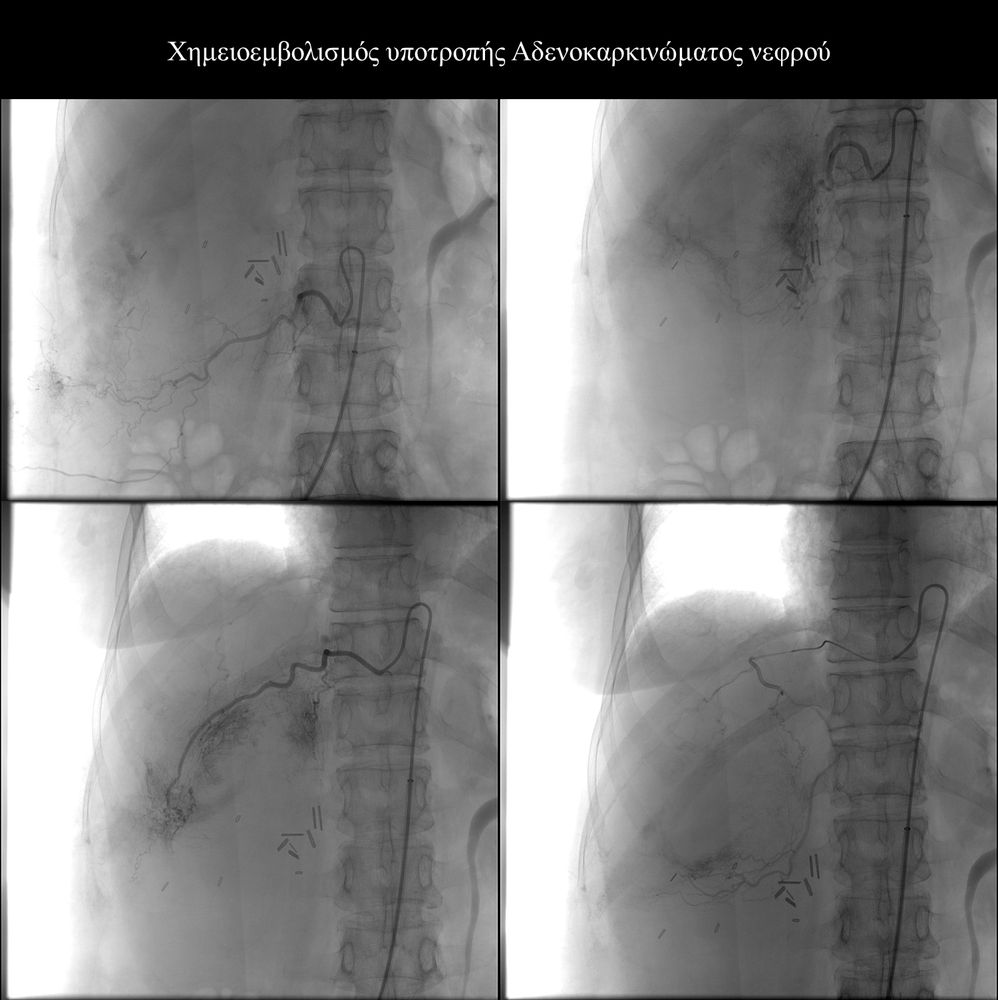

Ενδείξειςαποτελούν επίσης το χολαγγειοκαρκίνωμα και οι μεταστάσεις από καρκίνο του μαστού, καρκίνωμα νεφρού και σαρκώματα μαλακών μορίων.